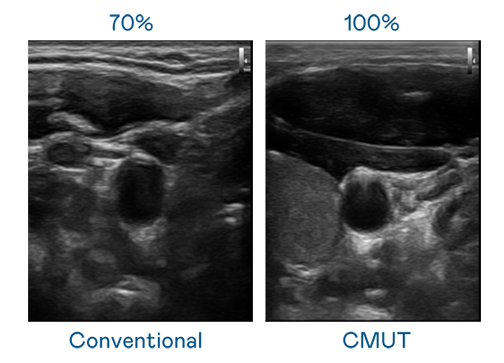

CMUT 技术是一种用电容式微机电元件来产生超音波讯号的技术。与传统 PZT 压电式技术相比,CMUT 频宽增加 30%,更宽频的超音波讯号让影像解析度大幅提升,是实现高影像品质医疗超音波扫描、促进精准医疗发展的关键技术。

大频宽带来超清晰影像

超音波影像的解析度高低,首先取决于探头能发出的讯号频宽。16岁免费版网站nba CMUT 可提供高清晰的超音波讯号,提供高频宽、高灵敏度、影像纹理细节更高的超音波影像,协助医护人员缩短影像判读时间及利用精准的医疗影像进行诊断。